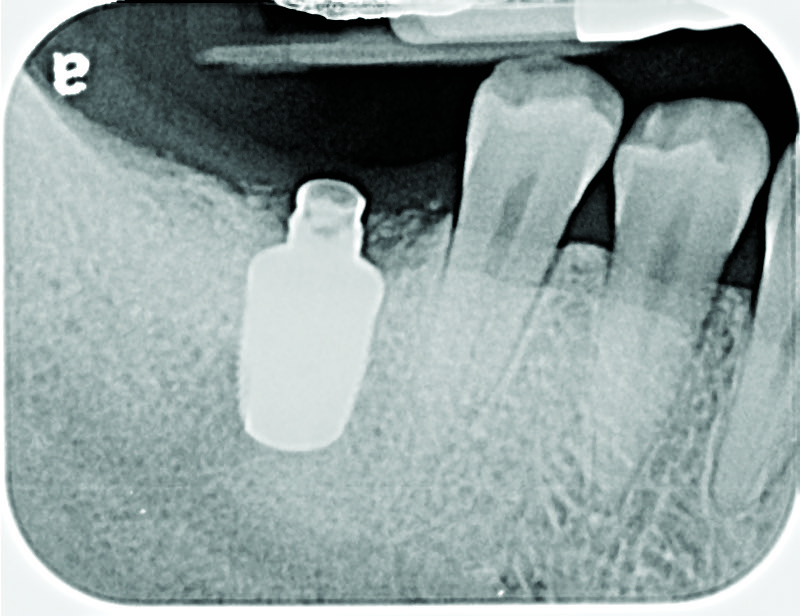

Fig 8. Loss of restoration and subsequent tissue overgrowth from broken abutment screw as shown in the radiograph (Fig 9).

Figure 8

Fig 9. Radiograph depicting fractured screw inside of the implant.

Figure 9

Fractured screws are challenging to retrieve, particularly when they are abutment screws. If the screw head is accessible, a hemostat can be used to remove it. However, when the screw breaks inside the implant (Figure 8 and Figure 9), removal can be highly complicated in order not to damage the implant’s internal threads. Therefore, many implant manufacturers have developed screw-retrieval kits. Because it is critical to be able to visualize the area, magnification using loupes and a surgical microscope may be necessary.8 Additional methods can be used to remove the fractured screw. A ¼ round bur set on a high speed can be used by lightly activating it, touching only the side of the screw. After repeating this technique several times, the screw may be able to be backed out with an explorer tip. Ultrasonic tips with copious irrigation may also dislodge the screw.7,20 In cases in which this fails, a small slot can be made in the head of the screw to back it out.21 If screw threads have been damaged during retrieval, they may be retapped using a tool obtained only from the implant manufacturer.7